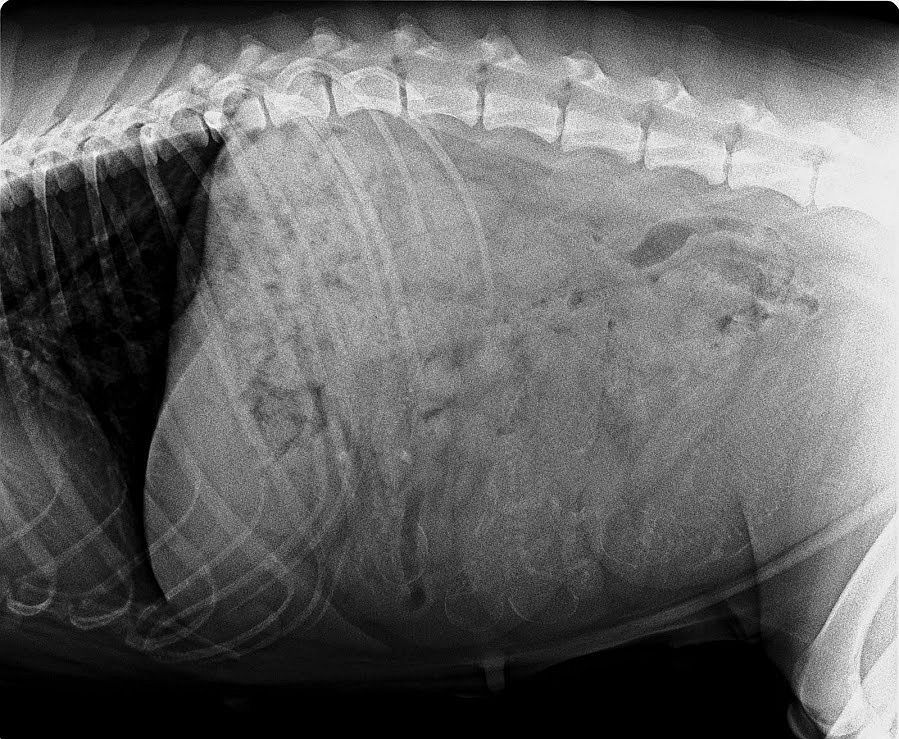

Am 15.4.2020 waren wir beim unserem Tierarzt zum Röntgen. Naja…fangt mal an zu zählen wie viel Babys Hedda in ihrem Bauch hat. Das ist gar nicht so einfach, das Bild ist ein bisschen unklar. Auch der Tierarzt konnte mir nicht die genaue Anzahl der Welpis verraten Hedda macht es echt spannend.

Und Frauchen muss sich in Geduld üben ☺……

Und da wir nun einmal beim Tierarzt waren musste Hedda auf die Waage.

Oh schreck☺…. 31,3 kg und sie hat noch 1 Woche bis die Mäusies geboren werden.

Aber egal…. Hedda geht es sehr gut. Sie ist nach wie vor Mega verschmust und der Hunger ist immer noch unstillbar☺☺☺